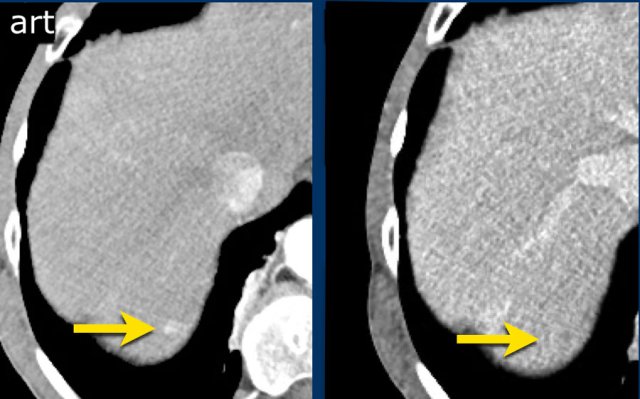

LRTR non-viable

The image in the late arterial phase show normal post treatment pattern with rim-like hyperenhancement of the surrounding liver parenchyma due to hyperemia after DEB-TACE (arrow).

DEB TACE is drug-eluting bead transarterial chemoembolization, a relative new endovascular treatment based on the use of microspheres to release chemotherapeutic agents within a target lesion with controlled pharmacokinetics.

DEB-TACE nowadays represents one of the most used treatments for unresectable hepatocellular carcinoma.

Arterial enhancing lesions which were treated with Deb TACE. There is mild perilesional enhancement noted on the follow-up scan, which is a normal post-treatment finding.

Area of arterial enhancement without washout in a segment 5 ablation defect (arrow), LRTR-equivocal.